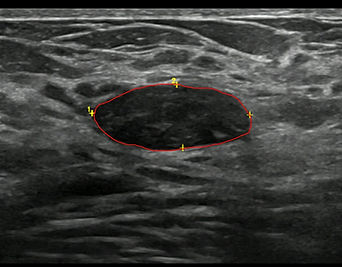

Kriyoablasyon sırasında oluşan buztopu'nun ultrason görünümü

Tedavi küçük bir iğne deliğinden girilerek gerçekleştirilir. Ultrason kılavuzluğunda fibroadenom içerisine yerleştirilen iğneler ile fibroadenom sıfırın altında -140 dereceye kadar soğutularak dondurulur. Bu yöntem ile fibroadenomun canlılığını yitirerek ölmesi sağlanmaktadır. Bu dondurma esnasında dokuda buz topu (Iceball) denen bir buz kütlesi oluşur. Bu buz kütlesi ultrason ile kolaylıkla görülebilmektedir. Bu nedenle işlem esnasında donan alanların rahatlıkla görülebilmesi sağlanmakta ve doğru yerin dondurularak yok edildiği işlem sırasında kontrol edilebilmektedir.